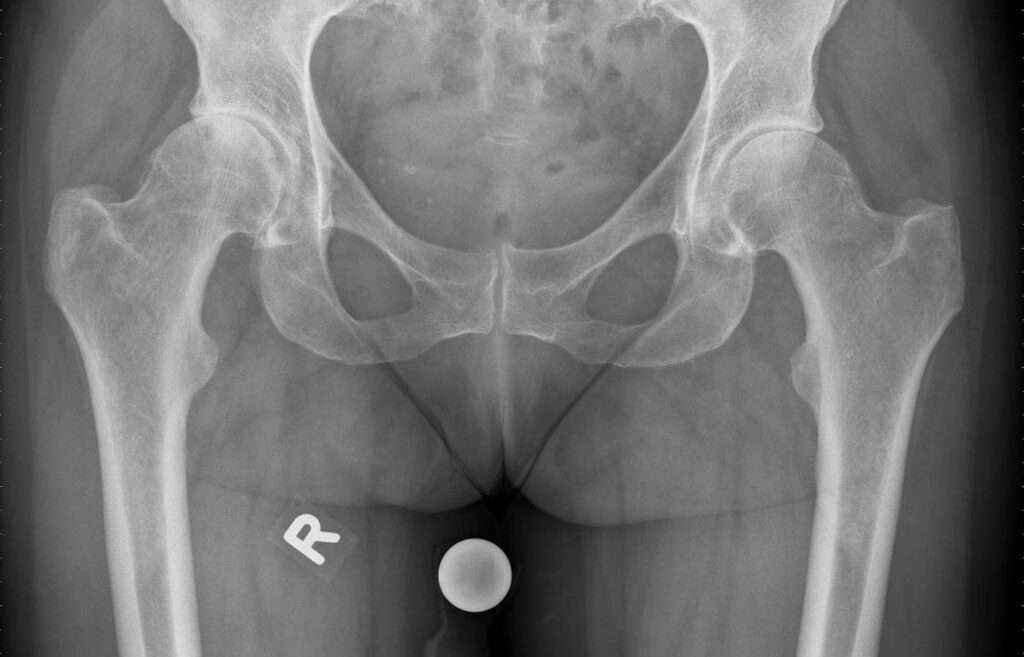

Röntgenbild vor Hüftgelenksprothese

Hüftarthrose rechts